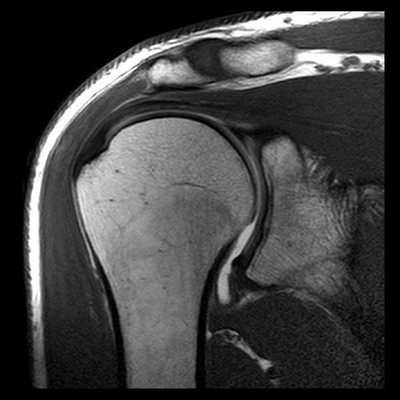

МРТ плечевого сустава в косой продольной проекции в норме

Первая из 24 последовательных Т1-взвешенных МР-томограмм правого плечевого сустава в косой продольной проекции с направлением срезов от медиальной стороны к латеральной. Томограммы получены с использованием плечевой катушки на 3Т МР-томографе. В наиболее медиальный срез попадает латеральный отдел легкого и грудная стенка. Широчайшая мышца спины покрывает нижнюю поверхность большой круглой мышцы. Эти мышцы сложно различить как отдельные структуры. Обе мышцы проходят в верхнелатеральном направлении и прикрепляются к гребню малого бугорка. К мышцам вращательной манжеты плеча относятся надостная, подостная, малая круглая и подлопаточная. Все мышцы вращательной манжеты начинаются от лопатки. Лопаточно-подъязычная мышца начинается от верхнего края лопатки. Она состоит из верхнего и нижнего брюшек. Верхнее брюшко прикрепляется к нижнему краю подъязычной кости. Лопатка имеет Y-образную форму вследствие наличия направленной кзади ости лопатки. В норме надостная мышца полностью находится внутри «Y» и заполняет весь ее объем, если не развивается атрофия мышцы. У верхней поверхности плечевого сустава можно увидеть часть трапециевидной мышцы. Трапециевидная мышца прикрепляется к верхнему краю латерального отдела ключицы, медиальному краю акромиона и верхнему краю ости лопатки. Дельтовидная мышца прикрепляется к тем же костным структурам рядом с трапециевидной мышцей, только к противоположной стороне каждой из костей (нижнему краю латерального отдела ключицы, латеральному краю акромиона и нижнему краю ости лопатки). Подлопаточная мышца заполняет подлопаточную ямку лопатки. Подостная и малая круглая мышцы расположены ниже ости лопатки. Подостная мышца крупнее и лежит выше малой круглой мышцы. Надостная, подлопаточная, малая круглая и подостная мышцы (по часовой стрелке) продолжаются в латеральном направлении. Сухожилия подостной и надостной мышц соединяются у латеральной поверхности головки плечевой кости. Ость лопатки заканчивается у акромиального отростка. Начинает визуализироваться акромиально-ключичный сустав. Сосудисто-нервный пучок проходит вдоль передней поверхности подлопаточной мышцы. Срез на уровне суставной впадины лопатки. Виден темный край проходящей по окружности суставной губы. От клювовидного отростка начинаются клювовидно-плечевая мышца и сухожилие короткой головки двуглавой мышцы. Суставно-плечевые связки визуализируются в виде пучков ткани с низкой интенсивностью сигнала, окружающих переднюю, нижнюю и задненижнюю поверхности плечевого сустава. Суставно-плечевые связки укрепляют капсулу сустава. Срез на уровне медиального края головки плечевой кости. Задняя артерия, огибающая плечевую кость, огибает шейку плечевой кости и анастомозирует с передней одноименной артерией. Вращательный интервал представляет собой треугольное пространство, ограниченное сверху передним краем сухожилия надостной мышцы, снизу—верхней поверхностью сухожилия подлопаточной мышцы, с медиальной стороны—основанием клювовидного отростка, а с латеральной стороны—сухожилием длинной головки двуглавой мышцы в межбугорковой борозде. Сухожилие длинной головки двуглавой мышцы начинается от над-суставного бугорка у верхнего края суставной впадины. На этом изображении оно проходит в дистальном направлении над головкой плечевой кости, окруженное синовиальной оболочкой. Сухожилие прободает капсулу сустава через отверстие, расположенное около межбугорковой борозды. На уровне середины головки плечевой кости дельтовидная мышца покрывает наружную поверхность плечевого сустава. Оценивать морфологический тип акромиального отростка лучше всего на первом срезе латеральнее акромиально-ключичного сустава. Вращательная манжета на уровне латеральной поверхности головки плечевой кости состоит преимущественно из сухожилий. Сухожилия начинают срастаться друг с другом и суставной капсулой. Уровень срезов приближается к латеральной поверхности головки плечевой кости. Сухожилия вращательной манжеты образуют непрерывный ободок тканей над головкой плечевой кости, а затем продолжаются в латеральном направлении. На этой Т1-взвешенной томограмме сигнал от сухожилий вращательной манжеты имеет более высокую интенсивность вследствие развития феномена «магического угла», в отличие от низкой интенсивности сигнала от сухожилий в норме. Нормальный сигнал от сухожилий можно увидеть при получении томограмм в режимах с большим эхо-временем. Сухожилия вращательной манжеты приближаются к месту прикрепления в области большого и малого бугорков. Сухожилие подлопаточной мышцы прикрепляется к малому бугорку и образует крышу межбугорковой борозды. Сухожилия надостной, подостной и малой круглой мышц прикрепляются к большому бугорку — к верхней, средней, и нижней поверхностям соответственно. Все еще видно прикрепление небольшой части пучков надостной и подостной мышц к большому бугорку. Наиболее латеральная поверхность плечевого сустава полностью покрыта средними пучками дельтовидной мышцы.